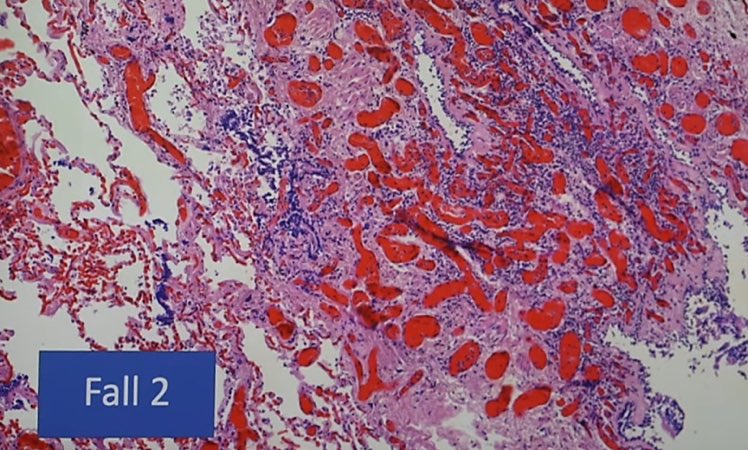

الآثار الجانبية المشتبه بها للقاح كورونا ذات العواقب المميتة المحتملة:

- ظواهر المناعة الذاتية ("الهجوم الذاتي")

-انخفاض القدرة المناعية ،

-التأثير على نمو السرطان.

-تلف الأوعية الدموية "التهاب البطانة" ، التهاب الأوعية الدموية ،